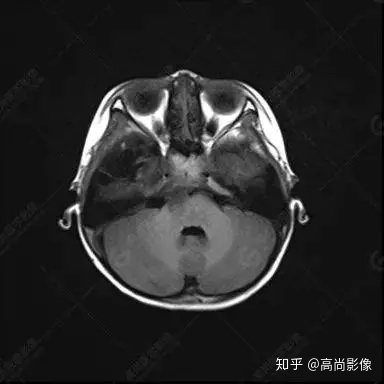

右側(cè)顳葉腫瘤切除術(shù)后(具體不詳):右側(cè)顳部骨質(zhì)不連續(xù)呈術(shù)后改變,右側(cè)顳葉術(shù)區(qū)見片狀長(zhǎng)T1長(zhǎng)T2信號(hào)影,F(xiàn)LAIR呈低信號(hào);術(shù)區(qū)后方右側(cè)顳枕葉見一巨大占位性病變影,邊界欠清,大小約6.2×5.8×4.3cm(前后×左右×上下),信號(hào)不均勻,T1WI呈等稍低信號(hào)間雜少許高信號(hào),T2WI呈高稍低混雜信號(hào),DWI示部分病灶彌散受限,相應(yīng)ADC圖減低,磁敏感序列見部分呈極低信號(hào),增強(qiáng)掃描可見明顯不均勻強(qiáng)化,鄰近硬腦膜及小腦幕增厚并明顯強(qiáng)化;另延髓右前方及右側(cè)橋小腦角區(qū)見一不規(guī)則形異常信號(hào)影,大小約3.2×1.3×3.7cm(左右×前后×上下),呈長(zhǎng)T1稍長(zhǎng)T2信號(hào),F(xiàn)LAIR呈等信號(hào),DWI未見受限,增強(qiáng)后明顯均勻強(qiáng)化,鄰近腦膜明顯強(qiáng)化。鄰近腦實(shí)質(zhì)及右側(cè)顳角明顯受壓;左側(cè)大腦半球未見局灶性信號(hào)異常,中線結(jié)構(gòu)稍左移。

右側(cè)顳葉腫瘤切除術(shù)后:現(xiàn)術(shù)區(qū)后方右側(cè)顳枕葉及延髓右前方占位,右側(cè)顳枕部硬腦膜及小腦幕明顯強(qiáng)化,結(jié)合既往影像資料,考慮為胚胎源性惡性腫瘤,如非典型畸胎樣/橫紋肌樣瘤(AT/RT)或原始神經(jīng)外胚層腫瘤(PNET)。